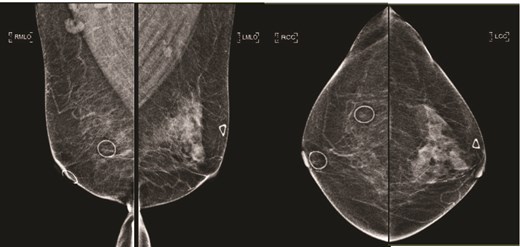

(Left) Mammography medioloateral oblique views of bilateral breasts; (Right) Mammography cranial-caudal views of bilateral breasts: Left upper central breast shows a vague focal asymmetry corresponding to the palpable concern, and several prominent right axillary lymph nodes.

(Left) Ultrasound images of the left breast ill-defined hypoechoic mass; (Middle, Right) Ultrasound images of the axillary lymph nodes with cortical thickening and effacement of the fatty hilum.